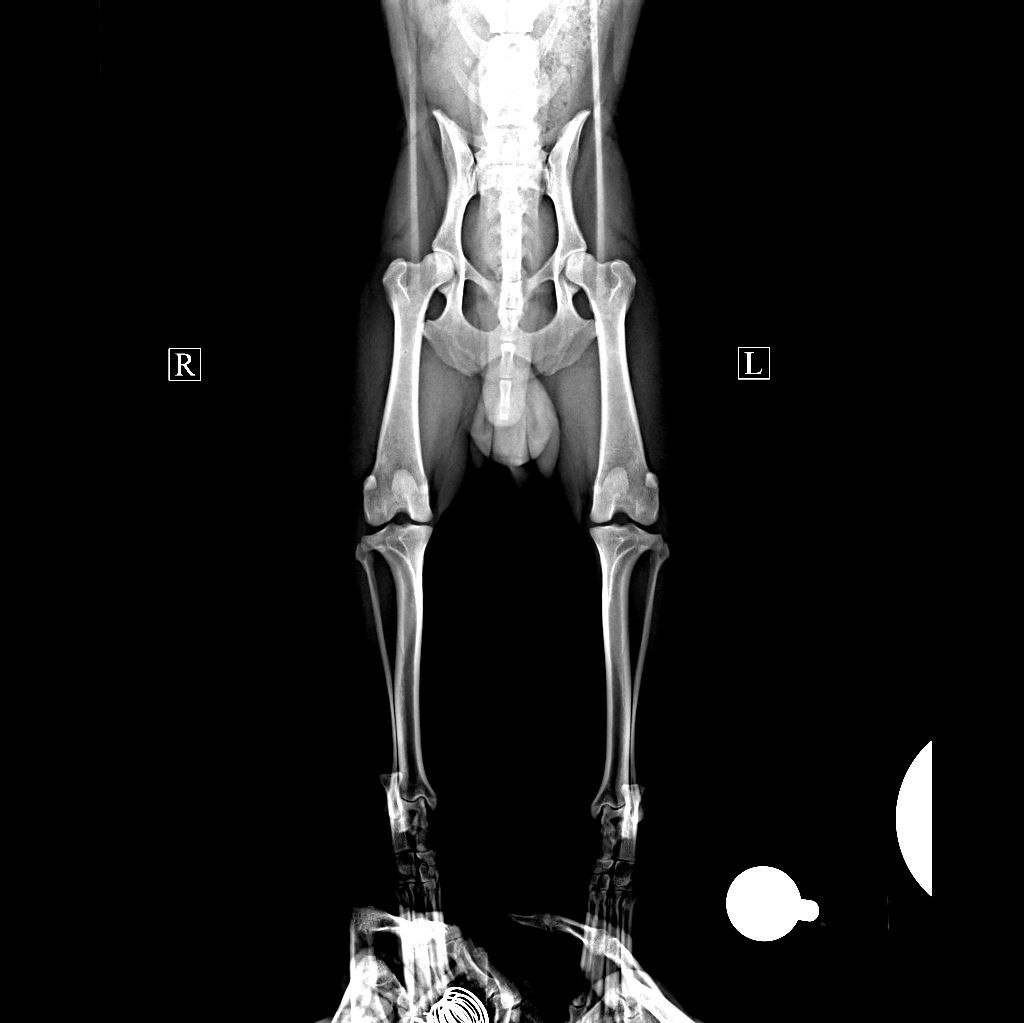

Завтра УЗИ и на четверг записались к Дудкину по лапе.

Мы не согласны и рентген надо сделать.